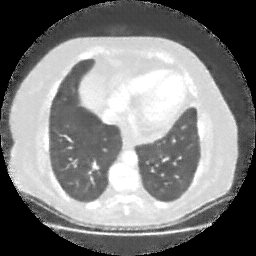

Generated VENOUS CT scan (A→B translation)

No window - Raw intensity values

Lung window (WL -600, WW 1500 β†’ Low βˆ’1350, High +150)

Mediastinum window (WL 40, WW 400 β†’ Low βˆ’160, High +240)